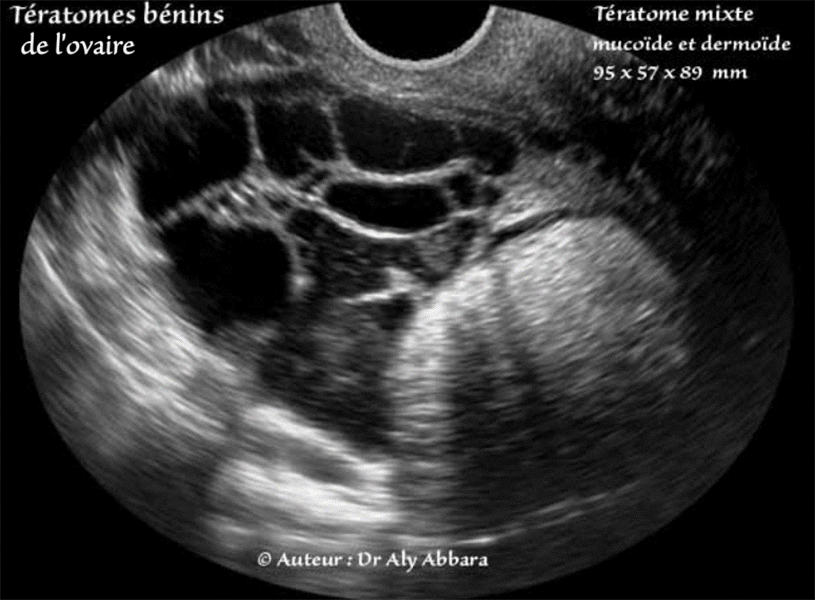

Tératome bénin de l'ovaire (kyste dermoïde) comportant une composante mucineuse (kyste mucineux bénin)

5 % des tératomes bénins de l'ovaire comportent une composante mucineux (cystadénome mucineux)

Autrefois, cette variété mixte fut appelée kyste dermomucoïde (Lebert, 1852)

Série d'images échographiques montrant les différents aspects et la composition d'une tumeur ovarienne

comportant deux composantes : dermoïde et mucineuse.

L'examen anato-pathologique de ce tératome bénin multissulaire est le suivant :

Tumeur kystique à surface est bosselée, mais sans végétation externe. La cavité principale contient un matériel jaunâtre pâteux constitué par du sébum et des cheveux. Plusieurs cavités accessoires renferment un contenu filant et translucide. Un fragment d'os et une dent sont visibles dans la paroi kystique.

Histologiquement, la cavité principale est tapissée par une bordure de type épidermique souvent détruite par réaction gigatocellulaire. Des annexes sudoripares et sébacées nombreuses sont visibles dans la paroi. D'autres cavité sont tapissées par bordure cylindrique mucipare parfaitement régulière reposant sur une bande de tissu conjonctif renfermant quelques adipocytes, quelques trousseaux musculaires lisses et occasionnellement quelques petites bandes de tissu glial.

Conclusion : dysembryome pluritissulaire complexe, mature (kyste dermoïde) de l'ovaire droit. Pas de signe histologique de malignité.